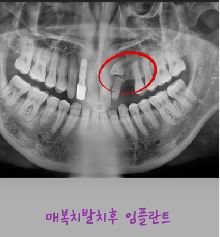

제목 매복발치후 임플란트

연수 퍼스트 치과에서는  난이도 있는 매복발치와 임플란트를~

3D CT 정밀 진단을 통해 신경과 뼈 상태를 정확히 파악하고

최소 절개로 안전하게 매복치를 발치한 후

잇몸과 뼈 상태에 맞춰 임플란트 치료를 체계적으로 진행합니다.

매복발치 후 임플란트는 난이도가 높은 치료인 만큼,

풍부한 임상 경험과 철저한 사후 관리가 중요합니다.

자연치아와 유사한 기능 회복과

오래 사용할 수 있는 안정적인 결과를 목표로 치료합니다.